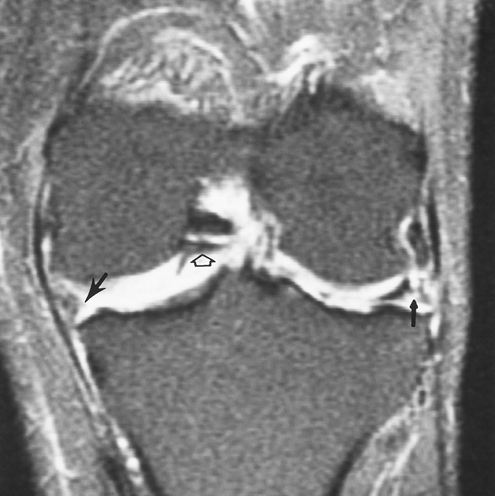

FIGURE 5-30 (A) Sagittal proton density-weighted image demonstrating the normal low-signal intensity of the ACL (arrows). (B) Acute ACL tear. Sagittal proton density-weighted image demonstrates an ACL tear (arrow). There is a joint effusion (open arrow) that is almost always present with an acute injury. Coronal fast spin-echo T2-weighted image (C) shows no visualized ACL (arrow), marrow edema in the lateral femoral condyle and tibia, and high-signal intensity along the MCL (arrow) caused by ligament sprain.